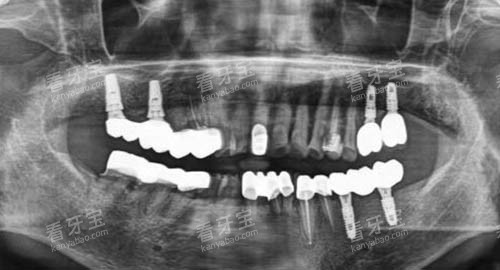

在牙齿种植方面,拥有较高的口腔 CT 设备,它能够清晰地呈现口腔内部的骨骼结构和神经分布,为医生制定精密的种植方案提供了有力的依据。

通过这台设备,医生可以更准地了解患者牙槽骨的密度、高度和宽度等信息,从而选择更合适的种植体和种植位置,大大提高了种植手术的成功几率。